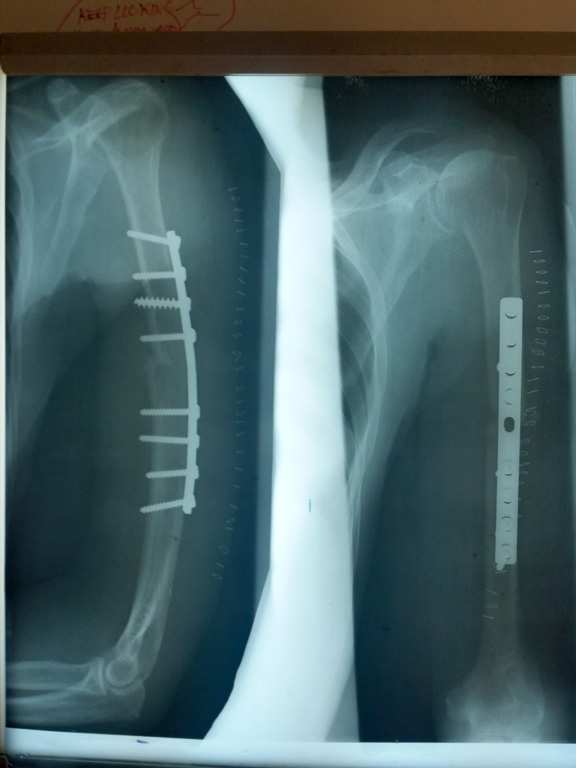

Fracture de l'humerus opéré

13